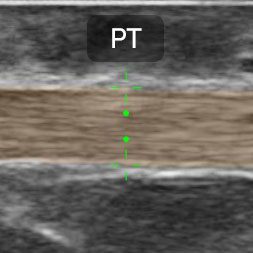

The new Clarius MSK AI features advanced artificial intelligence technology designed to identify, measure, and label key anatomical structures in real-time, providing accurate and reliable ultrasound information to clinicians. This not only speeds up workflows, but also boosts confidence in diagnosis and treatment plans. By outputting probabilities for each pixel within the image, the AI determines the particular tendon visible, allowing for quick and accurate assessments. Additionally, the AI makes it a valuable tool for training, allowing less experienced clinicians to learn and improve their diagnostic abilities with ease.

MSK AI identifies, measures, and labels key anatomic structures, starting with the patellar tendon, Achilles tendon, and plantar fascia using AI technology. Exclusively for Clarius members, the feature is designed to assist with musculoskeletal (MSK) scanning for specific anatomical sites, including the foot, ankle, and knee. With the colored overlay and automatically-placed calipers, it’s easier for novice users to learn ultrasound anatomy, and more efficient for experienced clinicians to conduct comparative and serial studies where consistent measurements of tendons are critical.

Automatically highlights the tendon, with adjustable opacity

Automatically measures the thickest width of the tendon

Labels the Patellar tendon, Achilles, and plantar fascia